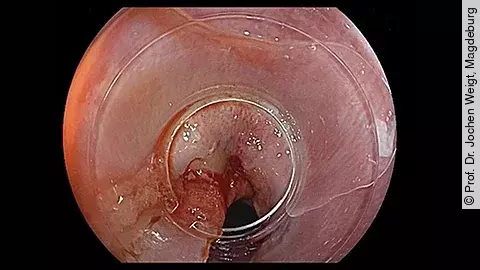

Endoskopisches LehrvideoTumor im Zökum

Ein genauer Blick lohnt sich bei unserem neuen endoskopischen Fall: PD Dr. Jochen Weigt präsentiert im Video einen Zufallsbefund bei einer 60-jährigen Patientin, die aufgrund eines positiven Hämoccult-Tests untersucht wurde. Neugierig? Dann gleich reinschauen!